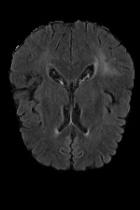

Current unsupervised anomaly localization approaches rely on generative models to learn the distribution of normal images, which is later used to identify potential anomalous regions derived from errors on the reconstructed images. However, a main limitation of nearly all prior literature is the need of employing anomalous images to set a class-specific threshold to locate the anomalies. This limits their usability in realistic scenarios, where only normal data is typically accessible. Despite this major drawback, only a handful of works have addressed this limitation, by integrating supervision on attention maps during training. In this work, we propose a novel formulation that does not require accessing images with abnormalities to define the threshold. Furthermore, and in contrast to very recent work, the proposed constraint is formulated in a more principled manner, leveraging well-known knowledge in constrained optimization. In particular, the equality constraint on the attention maps in prior work is replaced by an inequality constraint, which allows more flexibility. In addition, to address the limitations of penalty-based functions we employ an extension of the popular log-barrier methods to handle the constraint. Comprehensive experiments on the popular BRATS'19 dataset demonstrate that the proposed approach substantially outperforms relevant literature, establishing new state-of-the-art results for unsupervised lesion segmentation.